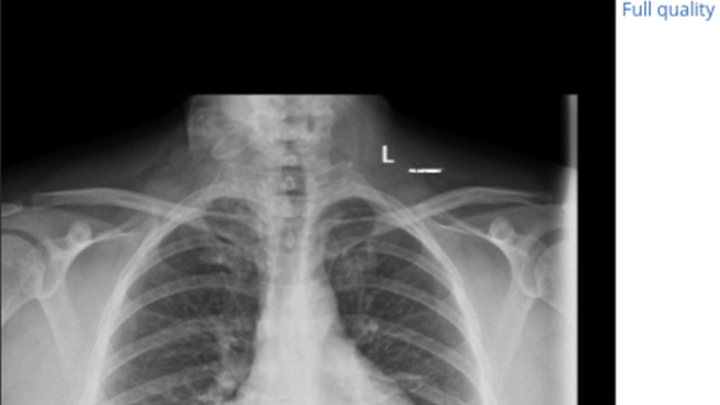

Last June I ended up in the ER because my toes and feet. Serious veinous insufficiency was diagnosed as Raynaud's but it's not. Eventually sent to vascular and Was offered surgery to try to reroute veins but declined because was unexpectedly pregnant. My feet, toes and legs freeze every day. They burn, they are numb and it hurts. Showers will help but it's a constant problem I have been learning to deal with. I've developed severe cramps in my toes, feet, hips, hands, and neck. It's to the point when they happen in my hands I can't move my fingers for a bit they get stuck. They say none of this is caused by the nodule but I don't believe it for a second. I tried taking tumeric last year for the inflammation and then felt this nodule burst and spray. I couldn't tell if it was in my throat or my lung, but I felt it and that was exactly a year ago last month. When it happened I heard some weird electrical noises in my chest and ever since I've been struggling with high blood pressure. It was because of that incident that they found my nodule and another incidental one in my lung. Eventually that will get checked but this one, this is the big one. The thyroid controls blood pressure it controls so much, yes they say my thyroid numbers are within range but my thyroid is not in the right range for the rest of my body and I need to be fixed. Last year on my birthday my Endo, Dr tang called said he was 70 percent sure it was cancer but then I ended up pregnant two days later and they wouldn't touch my nodule. After serious high risk miracle pregnancy here I am still waiting for removal! With my health a lot of surgeons are very hesitant.